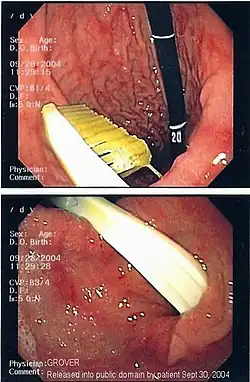

Commonly swallowed objects include coins, buttons, batteries, and small bones (such as fish bones),[1] but can include more complex objects, such as eyeglasses,[5] spoons,[6] and toothbrushes[5] (see image).

Endoscopic retrieval involves the use of a gastroscope or an optic fiber charge-coupled device camera. This instrument is shaped as a long tube, which is inserted through the mouth into the esophagus and stomach to identify the foreign body or bodies. This procedure is typically performed under conscious sedation. Many techniques have been described to remove foreign bodies from the stomach and esophagus. Usually the esophagus is protected with an overtube (a plastic tube of varying length), through which the gastroscope and retrieved objects are passed.[11]

Once the foreign body has been identified with the gastroscope, various devices can be passed through the gastroscope to grasp or manipulate the foreign body. Devices used include forceps, which come in varying shapes, sizes and grips,[12] snares, and oval loops that can be retracted from outside the gastroscope to lasso objects,[13] as well as Roth baskets (mesh nets that can be closed to trap small objects),[14] and magnets placed at the end of the scope or at the end of orogastric tubes.[12][15] Some techniques have been described that use foley catheters to trap objects, or use two snares to orient foreign bodies.[6]